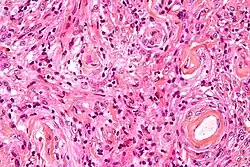

- A woven architectural pattern

- Psammoma bodies (spheroid calcifications)

- Syncytial cells (having indistinct cell membranes) with eosinophilic (pink) cytoplasms

- Round uniform nuclei

- Whorls (concentric cell arrangements)[16]

Meningiomas arise from arachnoidal cap cells,[17] most of which are near the vicinity of the venous sinuses, and this is the site of greatest prevalence for meningioma formation. Some subtypes may arise from the pial cap cells that migrate during the development together with blood vessels into the brain parenchyma.[18] They most frequently are attached to the dura over the superior parasagittal surface of frontal and parietal lobes, along the sphenoid ridge, in the olfactory grooves, the Sylvian region, superior cerebellum along the falx cerebri, cerebellopontine angle, and the spinal cord. The tumor is usually gray, well-circumscribed, and takes on the form of the space it occupies. They usually are dome-shaped, with the base lying on the dura.

Histologically, meningioma cells are relatively uniform, with a tendency to encircle one another, forming whorls and psammoma bodies (laminated calcific concretions).[19] As such, they also have a tendency to calcify and are highly vascularized.

- ^ Image by Mikael Häggström, MD. Reference for typical findings: Chunyu Cai, M.D., Ph.D. "Meningioma". Pathology Outlines.